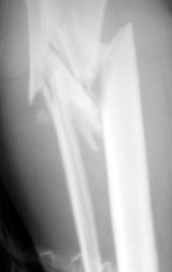

Re: открытый оскольчатый в/3 голени

Рентгенограмма при поступлении. Думаю на ней видно распространение линии перелома вниз